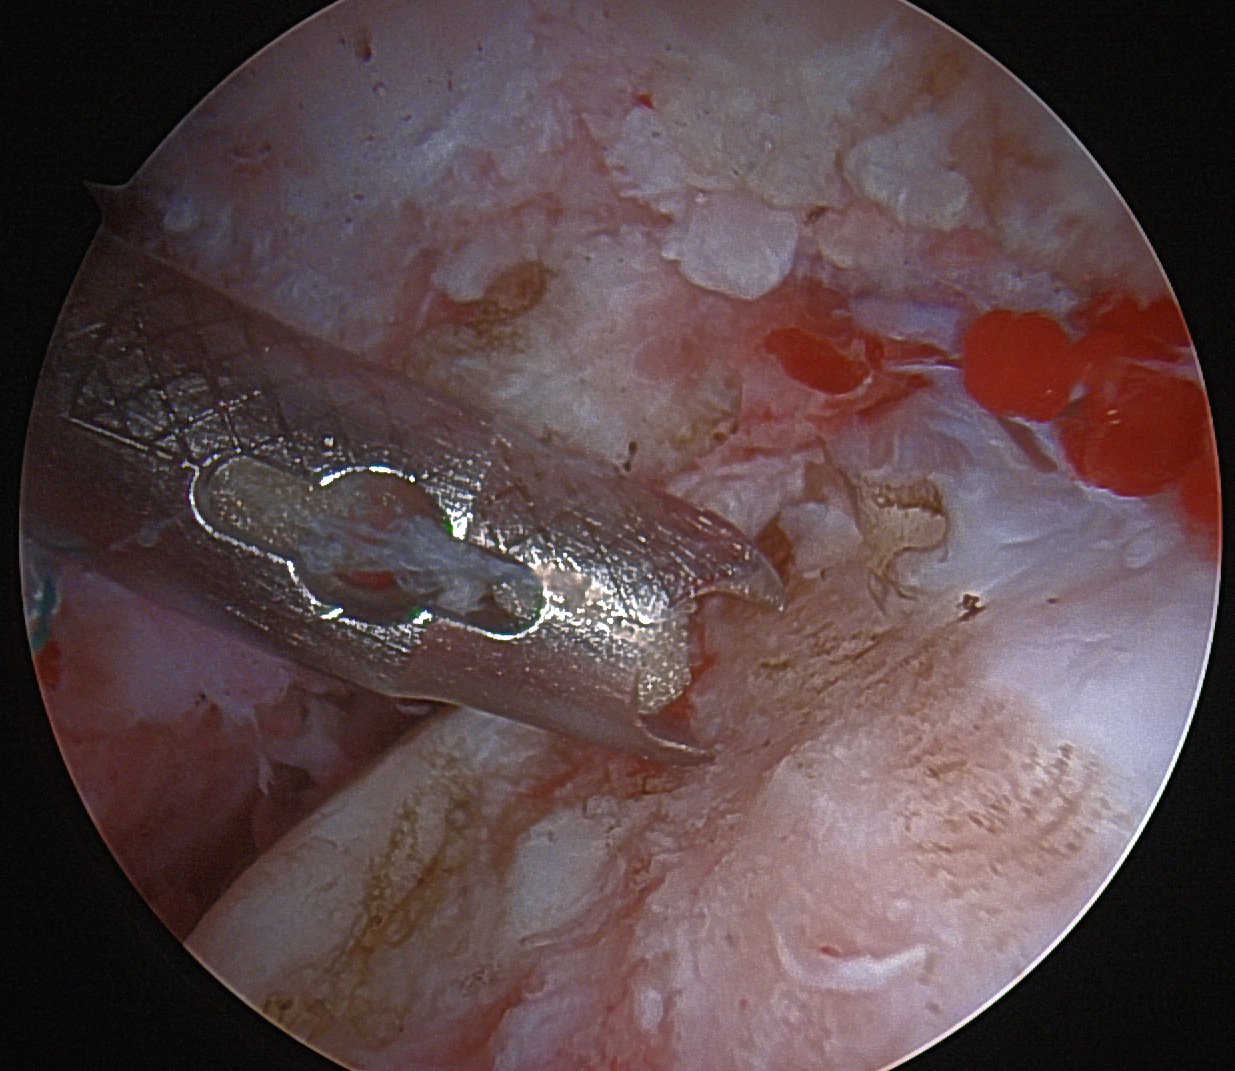

Arthroscopic multiple small drill holes techniques

Technique

- hip arthroscopy

- central compartment

- identify head neck junction

- multiple 1.5 mm drill holes into lesion in femoral head

- +/- BMAC

- retrospective study of CD versus multiple small drill holes

- 98 hips

- at 6 months better hip scores with multiple small drill holes